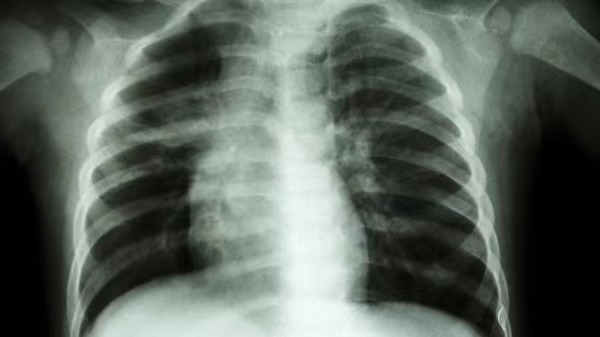

肺部ct显示,舟舟一侧肺部组织大面积变白。

接诊的儿科主任张雪荣经过一系列的查体后初步判断,舟舟已经发展成肺炎了。“收治入院后查胸片显示,孩子右肺内带见片状软组织样高密度影,右肺野内亦可见片状高密度影,右侧肋膈角变浅变钝,膈面模糊。考虑右肺部分不张伴胸腔积液可能。”看到胸片上舟舟的一侧肺部组织大面积变白后,家长既自责又后悔。好在经中西医结合治疗后,舟舟目前的症状已经明显好转。

这里科普一下,所谓的“白肺”是一种临床上的口语,并非指的就是人体的肺部组织变成白色了。

正常情况下,当肺泡里出现了炎症或者感染时,由于射线穿不透,所以在影像学里就会表现为白色区域。

而只有肺部的炎症比较严重,白色的影像区域面积达到了70%-80%时,医生们才会称之为“白肺”。